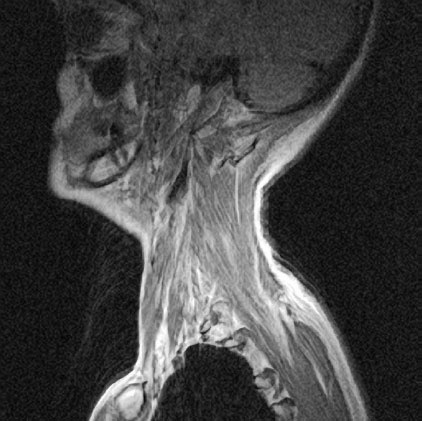

Рисунок 20. Мышцы боковой поверхности шеи и головы способны стимулировать шейные позвонки практически во всех мыслимых направлениях.

По той же причине особенно полезными оказываются упражнения на эксцентричное растяжение, т. е. с преодолением сопротивления (подобные тем, которые так распространены в йоге). Минеральная плотность кости связана с ее общей толщиной. Эксцентричное растяжение стимулирует кость сразу во многих местах, утолщая и упрочняя ее в целом и защищая от разноплановой нагрузки и напряжения. Противодействие продольной оси кости непривычным нагрузкам, что характерно для всех наклонов и растяжек в йоге, стимулирует образование новой костной ткани. По этим причинам она с большой вероятностью должна эффективно защищать от компрессионных переломов, которым особенно подвержены позвонки, в том числе шесть из семи шейных.